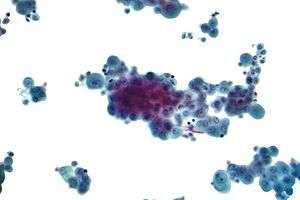

Micrograph of a pleural fluid cytopathology specimen showing malignant mesothelioma, one cause of a pleural effusion.